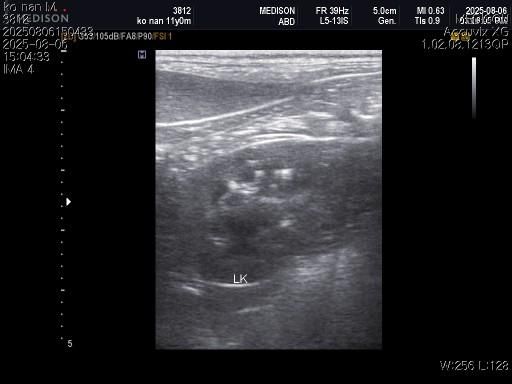

강아지 혈뇨의 원인을 찾고 있습니다 저희 강아지 두번도 아니고 딱 한번만 살려주세요..

1) 혈액검사와 엑스레이 그리고 초음파상 혈뇨의 원인이 나타나지가 않는지 궁금합니다.

3) 신장결석이 어느정도인지도 궁금합니다.